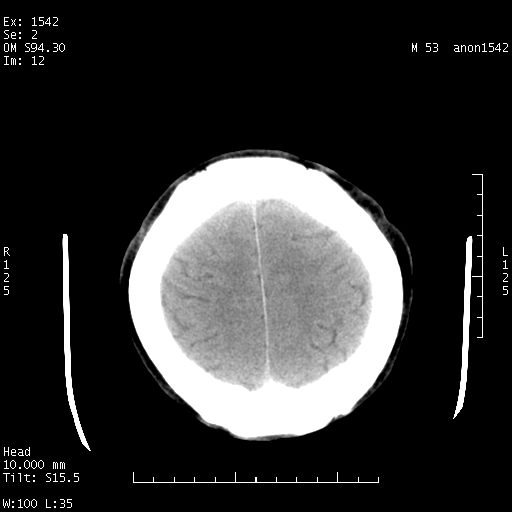

标题: CT10811:M53Y,头痛一月.其它没有什么 [打印本页]

标题: CT10811:M53Y,头痛一月.其它没有什么

左侧鞍旁不规则低密度,此区域和侧脑室有液平。若无外伤史。考虑左侧鞍旁表皮样囊肿自发破溃。

此图像一定有创伤史才对,病史对明确判断很重要

楼主应该把病史传好,有没有发热病史或是外伤病史。

考虑:左侧鞍旁表皮样囊肿自发破溃,是否合并感染?